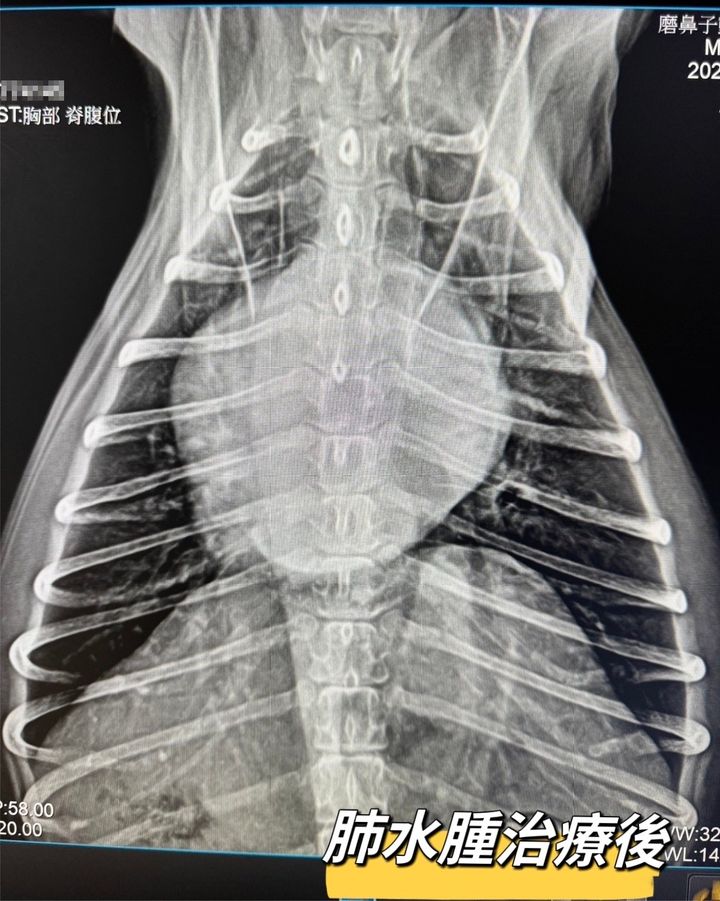

退行性二尖瓣疾病導致的肺水腫

Lucky最近出現咳嗽症狀,到了半夜更是沒辦法趴下休息心急的媽媽趕緊帶Lucky掛急診

經過

#胸腔X光 #心臟超音波 等檢查後

發現是退行性二尖瓣疾病(DMVD)導致「肺水腫」

趕快安排住進

#ICU氧氣病房

並進行相關治療

在醫療人員24小時不眠不休的照料下,毛孩很快就恢復穩定,順利脫氧出院囉

但日後也要開始按時服用心臟病藥物控制